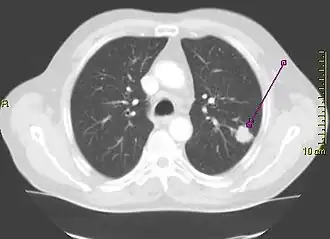

Computed tomography of the chest

Computed tomography of the chest or chest CT is a group of computed tomography scan protocols used in medical imaging to evaluate the lungs and search for lung disorders.

Contrast agents are sometimes used in CT scans of the chest to accentuate or enhance the differences in radiopacity between vascularized and less vascularized structures, but a standard chest CT scan is usually non-contrasted (i.e. "plain") and relies on different algorithms to produce various series of digitalized images known as view or "window". Modern detail-oriented scans such as high-resolution computed tomography (HRCT) is the gold standard in respiratory medicine and thoracic surgery for investigating disorders of the lung parenchyma (alveoli).